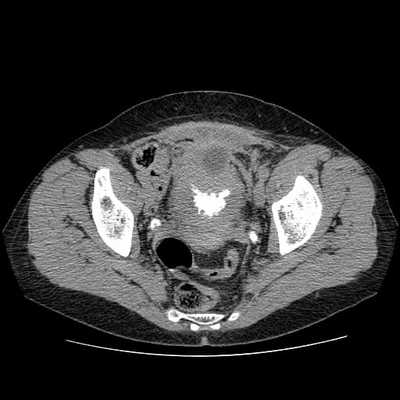

• Острый: утолщение стенки мочевого пузыря, ± гиподенсная стенка (вследствие отека), ± околопузырные воспалительные изменения

• Эмфизематозный: газ в стенках и просвете мочевого пузыря

• КТ с контрастированием:

о Острый: диффузное утолщение стенки мочевого пузыря, ± гиподенсные стенки мочевого пузыря (вследствие отека), ± гиперемия и инфильтрация околопузырной клетчатки

о Эмфизематозная фаза:

- Газ в стенках и просвете мочевого пузыря